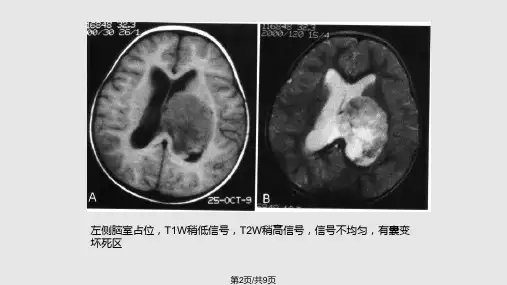

3、数目:4、形态特点:5、密度和信号特点:6、强化特点:7、DWI信号特点:8、磁共振波谱表现:9、其它有意义的征象:二、侧脑室肿瘤1、脉络丛乳头状瘤脉络丛乳头状瘤最常发生于侧脑室,偶可发生于三脑室。